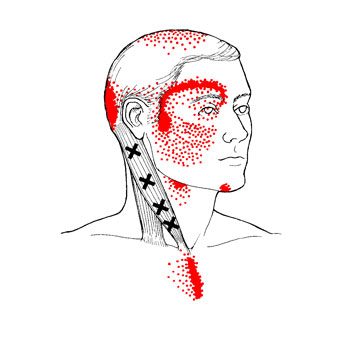

Oui! La douleur peut être causée par le syndrome myofascial et les points trigger myofasciaux. Ce n’est pas une maladie imaginaire, le syndrome myofascial et les points myofasciaux existent vraiment et malheureusement ils sont peu connus de notre système de santé traditionnel. Ils peuvent vous rendre la vie misérable. Eh, oui! Les points trigger ont passé l'art de mimer les symptômes de certaines maladies, de quoi laisser perplexe le meilleur des médecins.

Pour moi qui suis massothérapeute, ils font partie de mon quotidien. Je traite des gens à tous les jours avec des douleurs aux épaules, au cou, aux genoux, mal de dos, etc. Il m’arrive souvent de voir des gens qui ont très mal et qui ne savent plus quoi faire pour soulager leurs maux. Malheureusement, la massothérapie est souvent leur dernier recours. Ils ont souvent tout essayé, mais leurs douleurs persistent. Dans bien des cas il s’agit d’un durcissement du fascia et de points trigger. De deux à trois traitements suffirent dans bien des cas pour qu’ils retrouvent leurs qualités de vie qu’ils avaient auparavant.

Ils me disent tous la même chose! J’aurais dû venir te voir avant, car j’ai dépensé une fortune en médicament et en traitement! Alors la prochaine fois que vous avez une douleur quelconque, il se pourrait bien que la cause soit le syndrome myofascial et les points trigger myofasciaux!